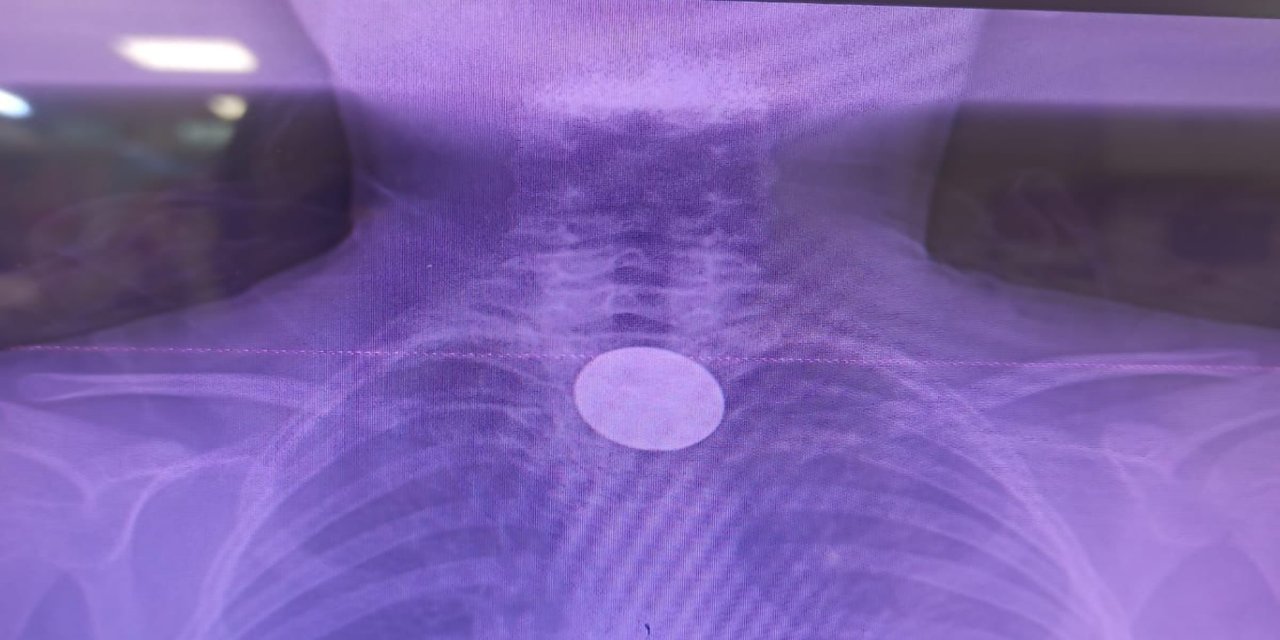

Siirt’te küçük çocuğun yuttuğu madeni para başarılı operasyonla çıkarıldı